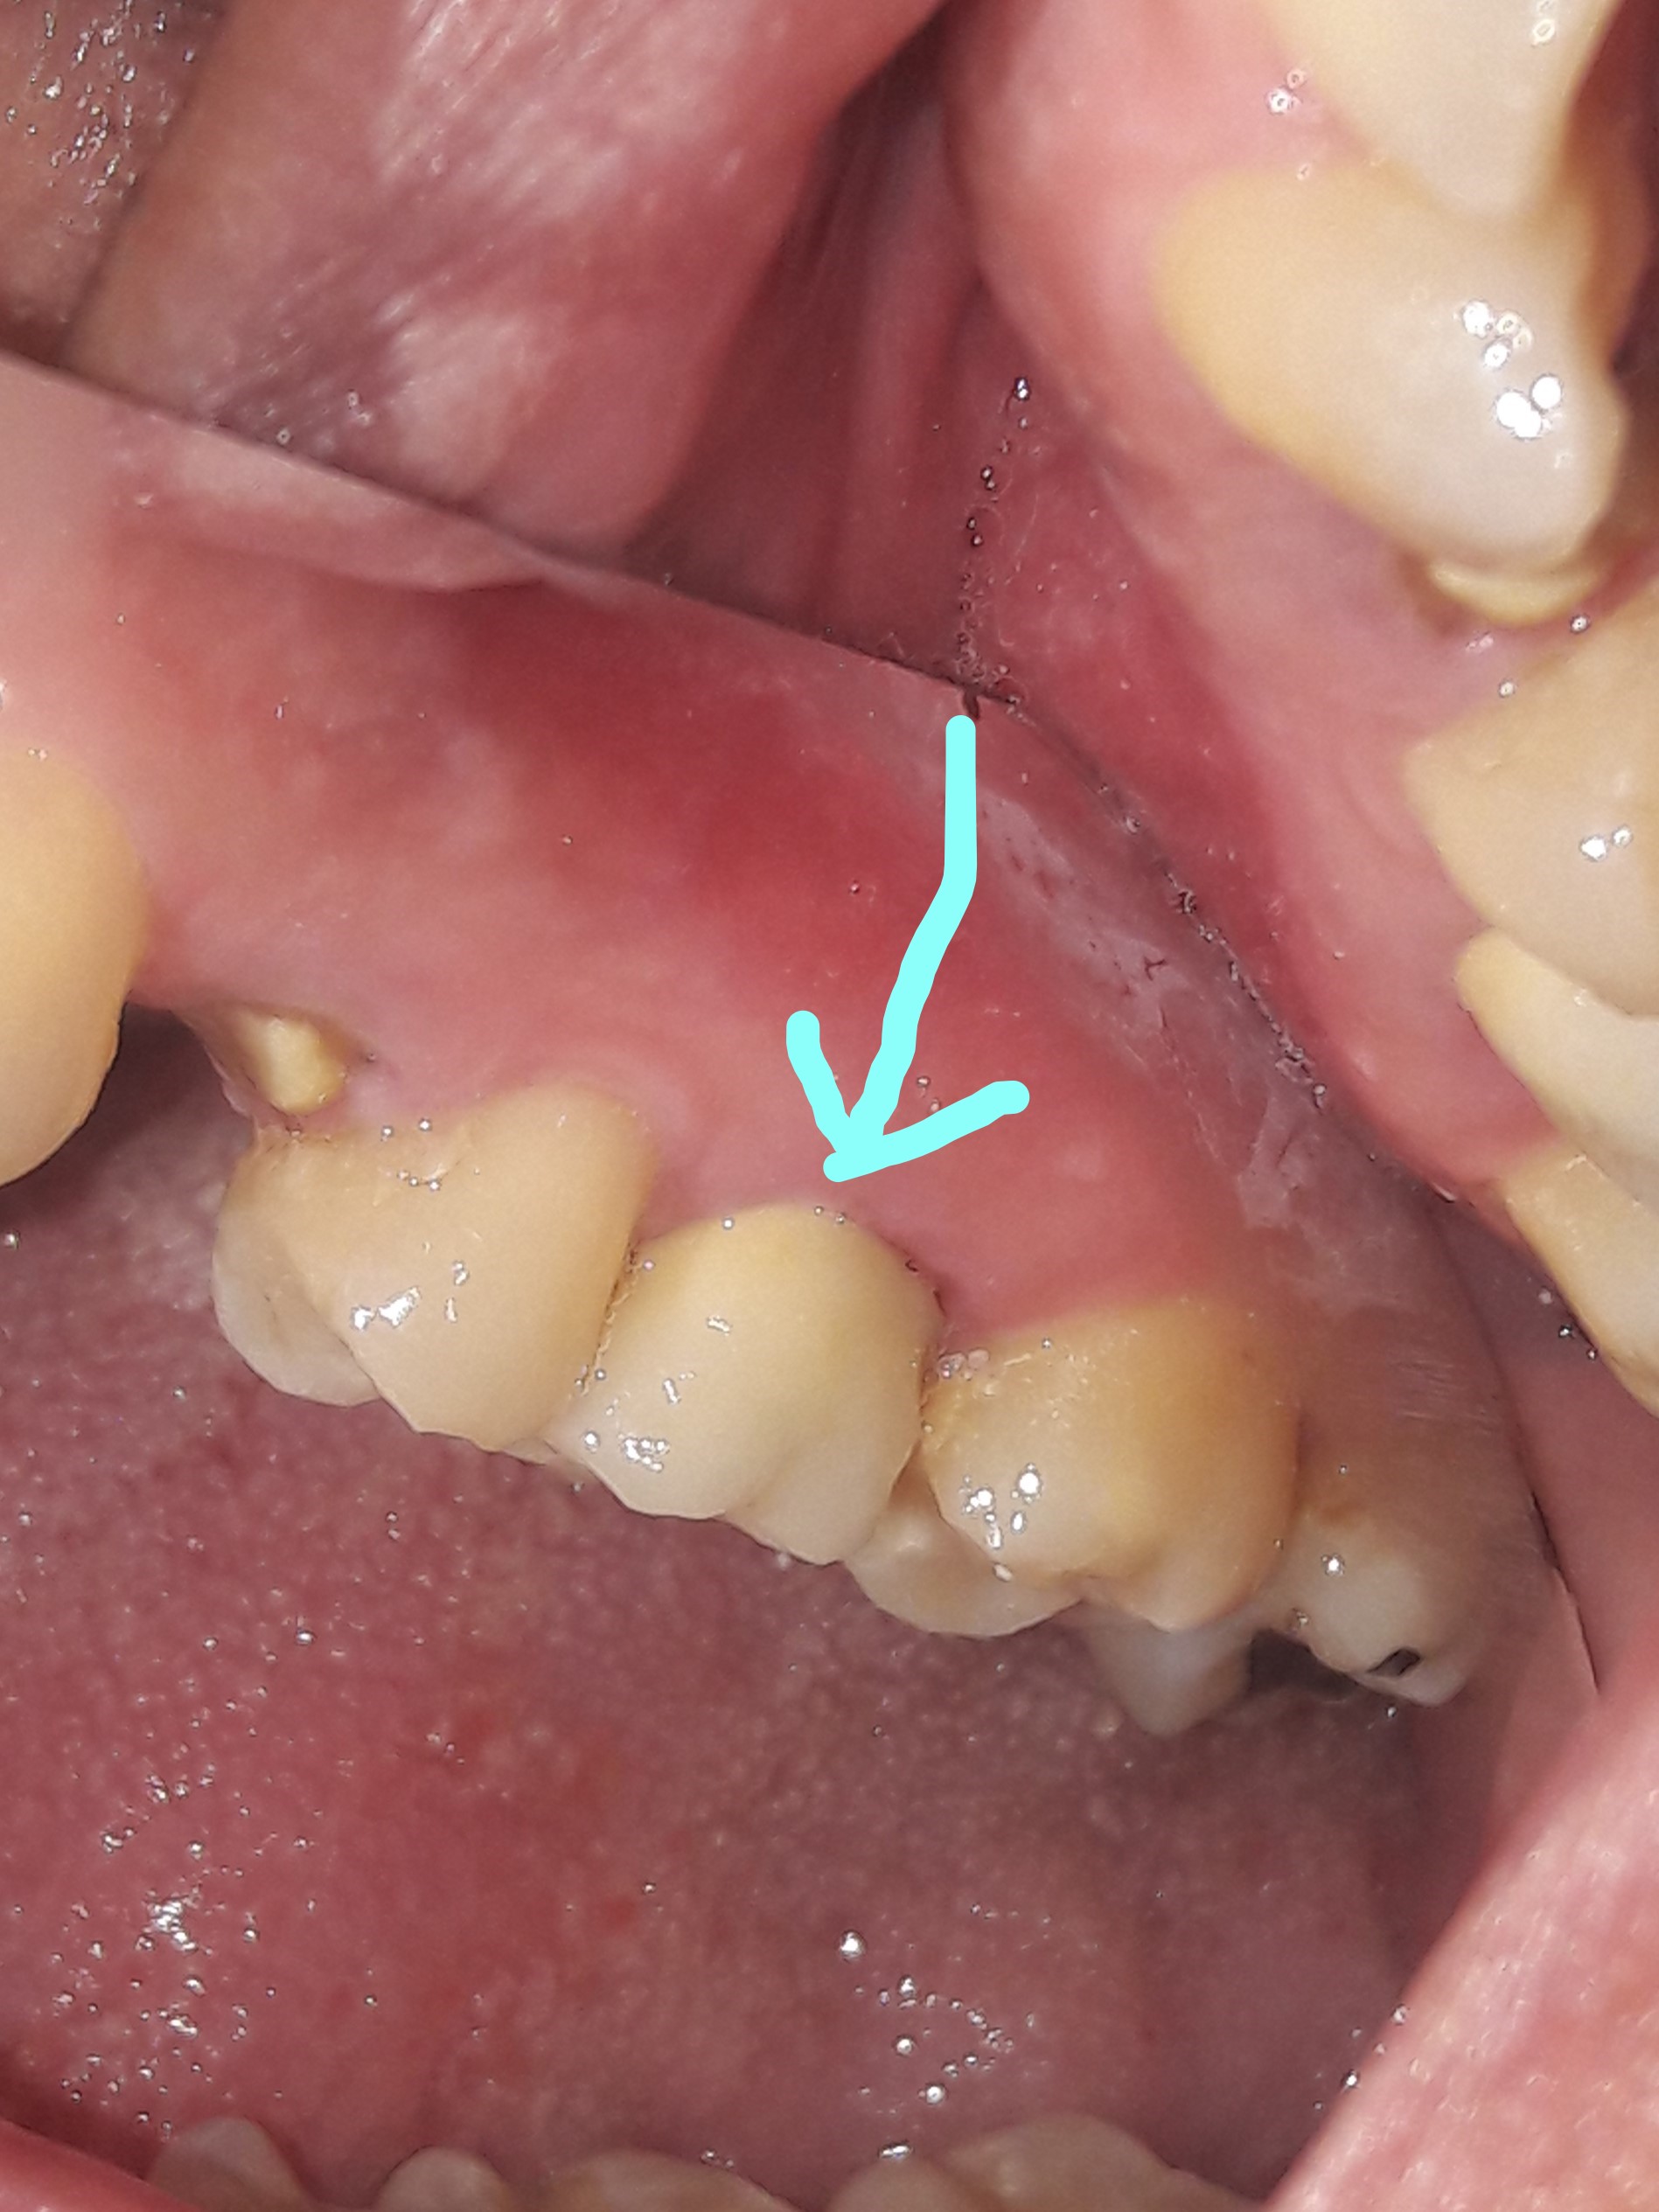

Ο πρώτος γόμφιος στην αριστερή πλευρά της κάτω γνάθου είχε απονευρωθεί στο παρελθόν. Ο ασθενής δεν θέλησε να καλύψει το δόντι με θήκη, ώστε να είναι πλήρως προστατευμένο με αποτέλεσμα το δόντι να σπάσει (όπως φαίνεται στην αρχική εικόνα). Η λύση θεραπείας ήταν η κατασκευή στεφάνης δοντιού, αφού προηγουμένως το δόντι τροχίστηκε καταλλήλως και ο οδοντοτεχνίτης κατασκεύασε την ολοκεραμική θήκη ζιρκονίου.

ΠΡΙΝ